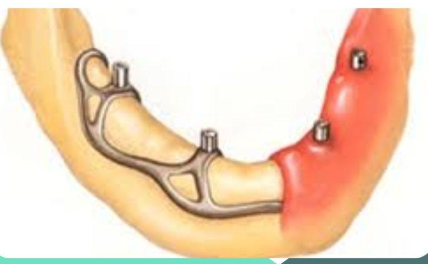

What are subperiosteal implants (eposteal)?

Beneath the periosteum (Placed above rather than within the jaw bone. They are placed below the gums)

What are subperiosteal implants made of?

Cast metal framework in Chrome Cobalt or Titanium

What is the main surgical challenge of subperiosteal implants?

It is a complicated and painful surgical technique requiring a major flap and impression of the alveolar bone

How is the subperiosteal implant framework supported?

It rests directly on the alveolar bone without any mechanical anchoring components

Titanium framework with HA coating

Panoramic view after placement